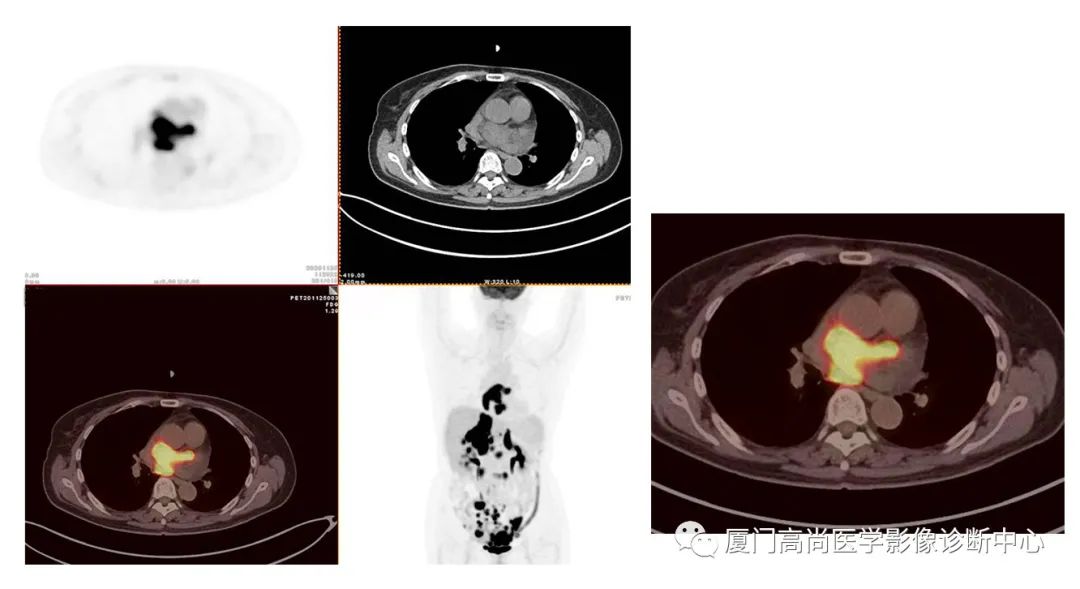

左心房淋巴瘤病灶

右心房淋巴瘤病灶

PET/CT發(fā)現(xiàn) :左心房、右心房見團塊狀FDG攝取增高;雙側(cè)腎上腺增大,F(xiàn)DG攝取增高;膽囊和胃壁結(jié)節(jié)樣FDG攝取增高;小腸多節(jié)段腸壁增厚,F(xiàn)DG攝取增高;腹膜后、腹腔及盆腔多發(fā)淋巴結(jié)腫大,F(xiàn)DG攝取增高;上述考慮為淋巴瘤

經(jīng)腎上腺穿刺活檢 :病理證實為彌漫大B細(xì)胞淋巴瘤